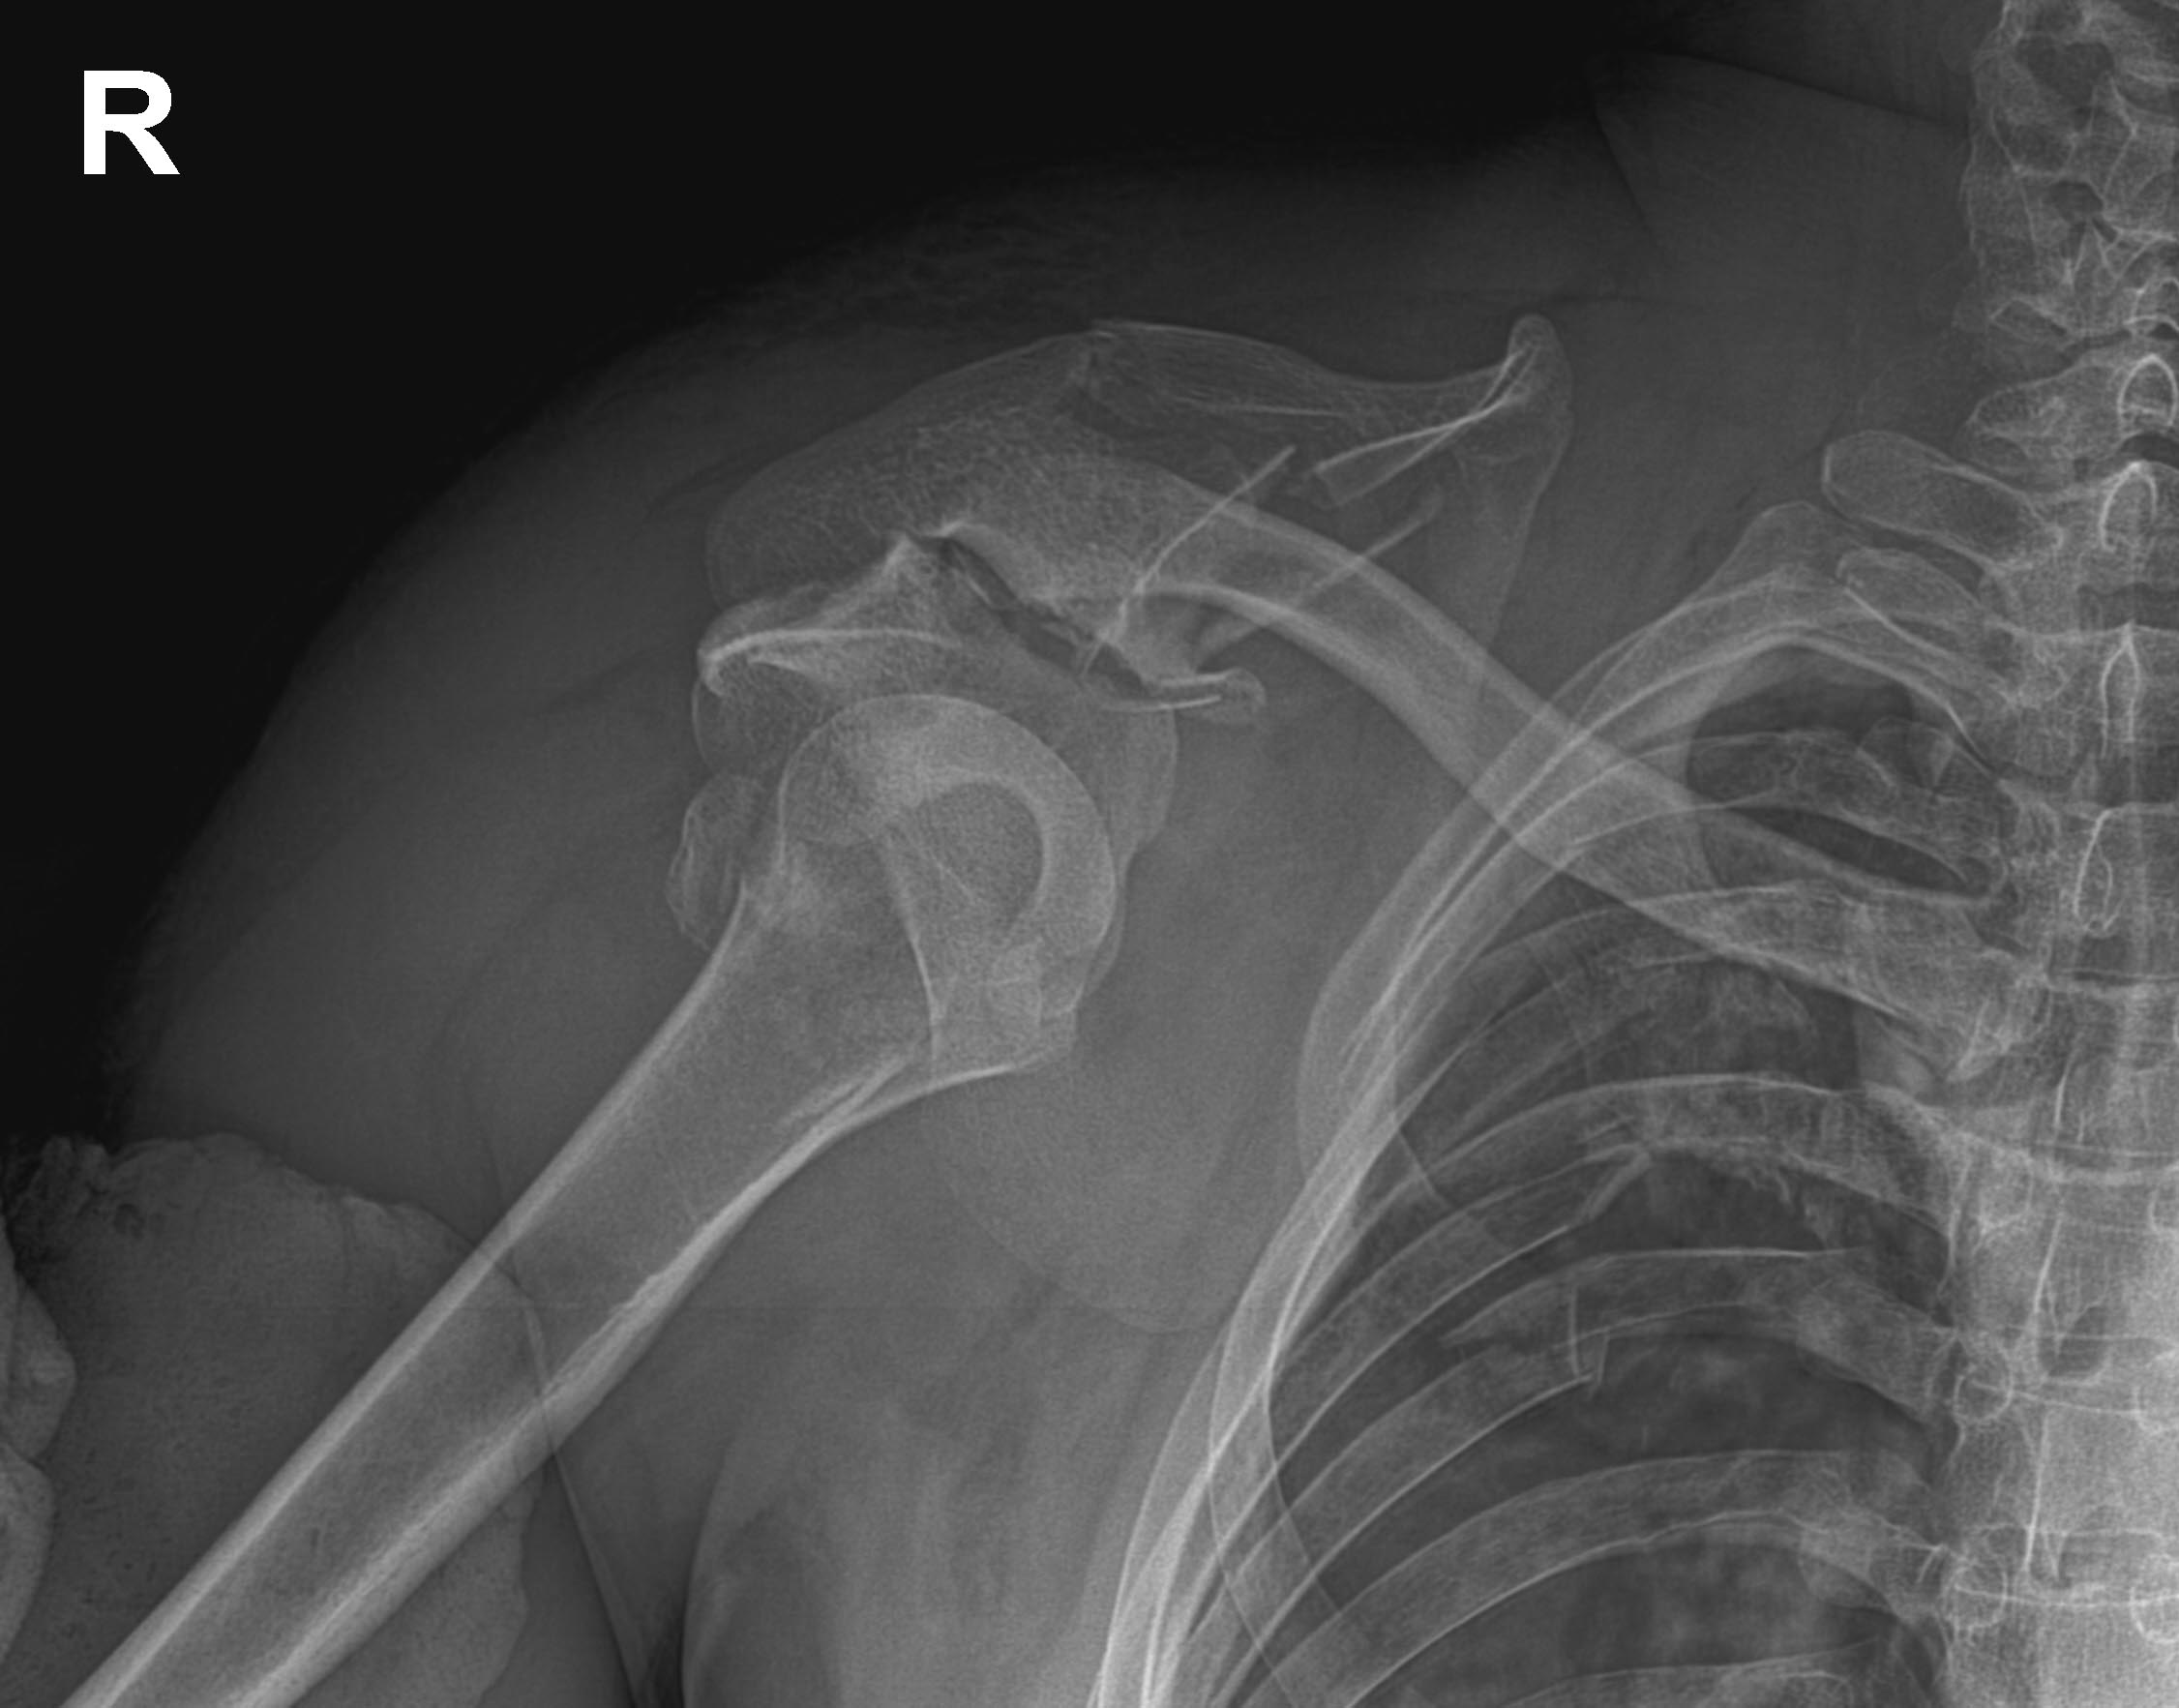

Механизм травмы, скорее всего, трактирный. Похоже на незавершенный отрыв плечевого пояса. Ключица только уберегла от полного. Должны быть проблемы с нервно-сосудистым пучком.

спасибо коллеги что откликнулись.по ссылке материал гляну обязательно! вывих не вправляется так как нет опоры гленоид с коракоидом отвалились ,ключица вывихнута. ссадины подлечим и будем оперировать. проблем с сосудисто нервным пучком нет!)

уважаемые коллеги спасибо за участие прооперировали пациента ,вывих плеч удалось вправить во время синтеза лопатки из доступа Жюде.

потом перевернули и из детьтоидопекторального подшили ротаторы с кусками бугра. вывих ключицы не фиксировали.позже сделаем